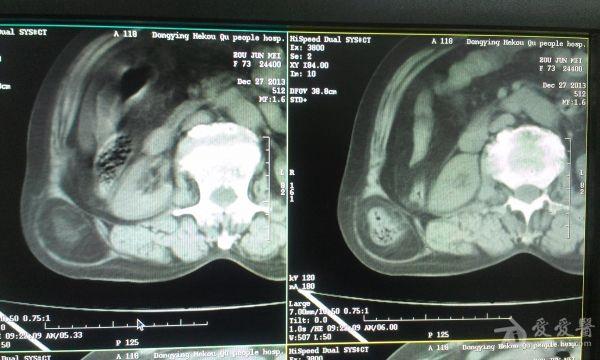

挺经典的腰疝

右腰部包块,随呼吸可运动。

非常经典的ct片,不知是继发于何种原因还是先天性的?里面内容物一般是肠管,很少发生较窄、嵌顿。